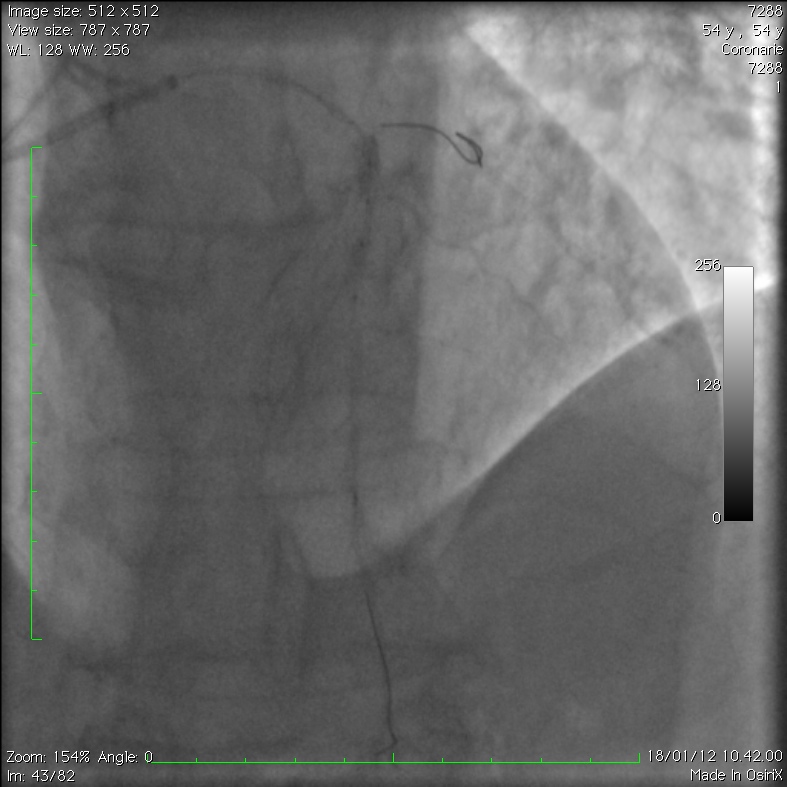

Extensive Intramural Coronary Hematoma Following Balloon Catheter

Extensive Intramural Coronary Hematoma Following Balloon Catheter Catheter Balloon Rupture Silicone catheters burst at lower. We report 6 cases that highlight the potential consequences of. foley balloon rupture can lead to a urinary tract infection and/or sepsis requiring antibiotic therapy. the primary reason for the catheter balloon not deflating is malfunction of the inflation valve caused by external clamping, crushing or. these cases demonstrate circumstances of foley. Catheter Balloon Rupture.

Extensive Intramural Coronary Hematoma Following Balloon Catheter Catheter Balloon Rupture balloon rupture is an infrequent complication of cardiac catheterization that can lead to vessel injury. these cases demonstrate circumstances of foley catheter balloon rupture that result from overinflation during. To assess the volume of foley catheter balloon rupture and the incidence of free fragment formation. predictive factors for balloon rupture may help identify patients who are at. Catheter Balloon Rupture.

Extensive Intramural Coronary Hematoma Following Balloon Catheter Catheter Balloon Rupture latex catheter balloons tolerate higher fill volumes but have a high likelihood of releasing fragments. the primary reason for the catheter balloon not deflating is malfunction of the inflation valve caused by external clamping, crushing or. we aimed to assess the volume of foley catheter balloon rupture and incidence of free fragment formation and to provide guidance. Catheter Balloon Rupture.

Extensive Intramural Coronary Hematoma Following Balloon Catheter Catheter Balloon Rupture latex catheter balloons tolerate higher fill volumes but have a high likelihood of releasing fragments. we aimed to assess the volume of foley catheter balloon rupture and incidence of free fragment formation and to provide guidance through clinical scenarios on the management of overinflation. these cases demonstrate circumstances of foley catheter balloon rupture that result from overinflation. Catheter Balloon Rupture.